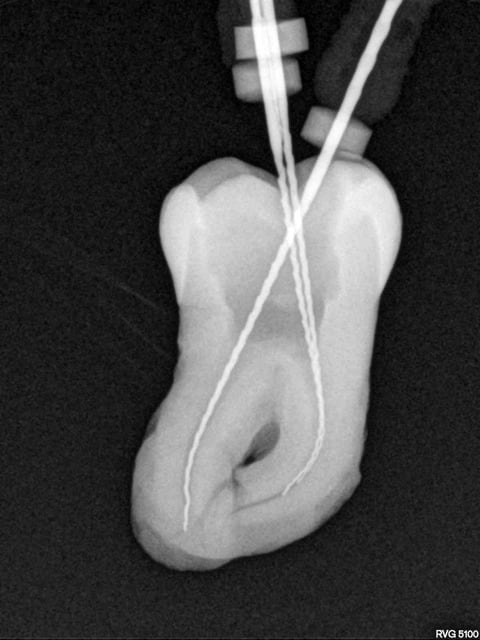

Une belle instrumentation en mésial, quelle tristesse.

Tout allait bien en progressant à patte de velours jusqu'à l'alésoir 30-4 trop fatigué apparemment (FKG Race), et j'ai donné un peu trop de force dans la progression verticale.

J'ai essayé de déloger la lime, j'ai cassé la deuxième puis la troisième.

Bon le canal est propre à défaut d'être étanche.